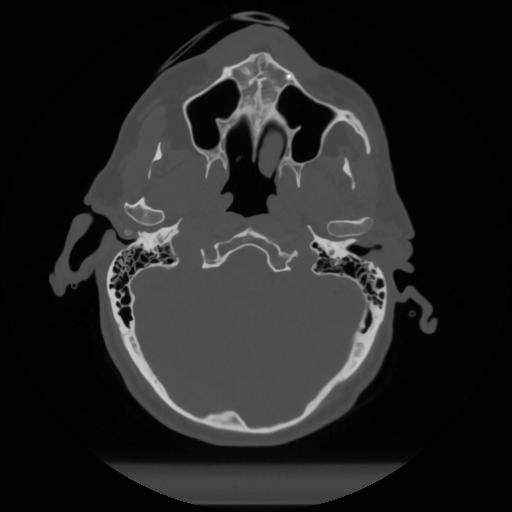

12 P.BLANDAS,,Vol,0.5,P.BLANDAS,,